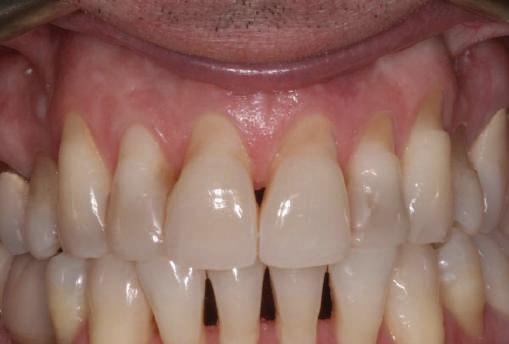

Fig. 1 prezintă pacientul după inserarea primului set de bonturi implantare individualizate; dinţii naturali adiacenţi

sunt încă prezenţi pentru a susţine puntea provizorie.

Şapte luni mai târziu (fig. 2), acele bonturi individualizate din prima etapă au manifestat semne de recesie de 1-3mm. Atitudine: S-a decis reprepararea intraorală a tuturor bonturilor (fig. 3), astfel încât toate marginile bonturilor să fie la nivelul sau sub marginea gingivală (de notat că 1.1. şi 2.1. au fost submersaţi ulterior pentru a avea sprijin implantar deplin).

Deşi reprepararea a îmbunătăţit marcat estetica finală, a necesitat aplicarea şnurului de retracţie, amprente noi şi turnări noi.

Cazul (1): Reprepararea intraorală a bonturilor Figurile

1. Aspect după inserarea primului set de bonturi implantare individualizate.

2. După 7 luni, bonturile individualizate din prima etapă au prezentat recesie de 1-3mm.

3. Bonturile repreparate intraoral.